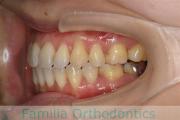

上の前歯の並びが気になるのできれいにしたい、ということで来院されました。マウスピース型矯正装置のひとつ、インビザライン/InvisalignR(薬機法および医薬品副作用被害救済制度の対象外)を用いて治療しました。

非抜歯で2年弱、20回程度の通院で治療が完了しました。

マウスピース矯正は、患者さんの協力に治療結果が左右されるところはリスクと言えるかもしれません。

上顎

下顎

前歯の関係など

右側

正面

左側